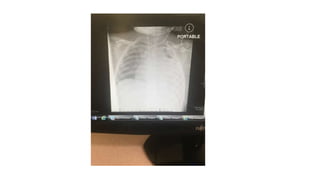

Chest US ,CT both suggest a pleural effusion (proteinacious) with

minimal septae

Chest US ,CTboth suggest a pleural effusion (proteinacious) with minimal septae